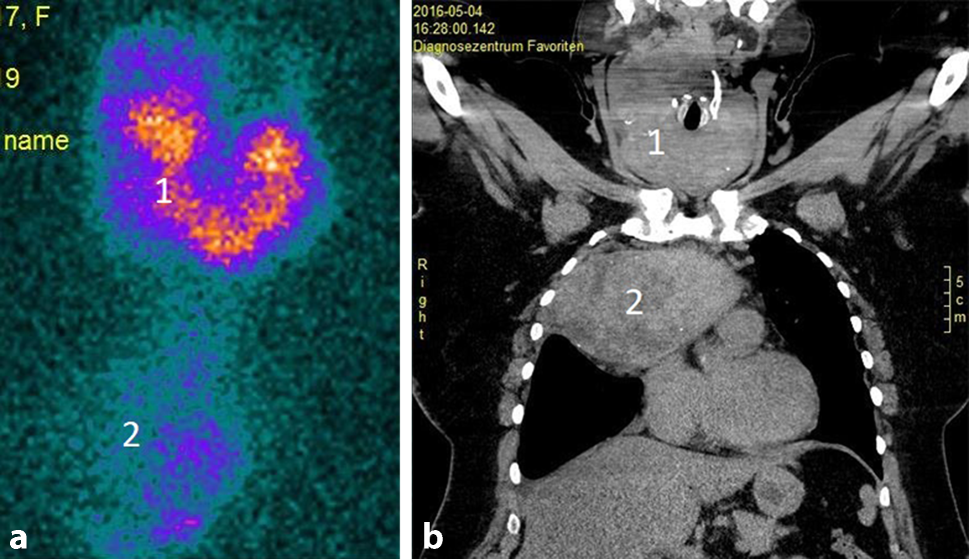

Inwieweit präoperativ zusätzliche nuklearmedizinische Untersuchungen oder eine nuklearmedizinisch-radiologische Fusionsdiagnostik zur Erfassung der Ausdehnung des Krankheitsbildes sinnvoll sind, muss interdisziplinär zwischen Chirurgen, Nuklearmedizinern und Radiologen besprochen werden. Bei medullären Schilddrüsenkarzinomen ist ein DOPA-PET-CT für die OP-Planung und das Resektionsausmaß jedenfalls hilfreich (Abb. 7). Insbesondere von Bedeutung ist die Ausnützung aller diagnostischen Möglichkeiten vor Re-Eingriffen.

Abb. 7

Das Dopa-PET-CT zeigt das Ausmaß des medullären Karzinoms und seiner Metastasierung: zentraler und links lateraler Hals; nach 3‑Kompartementlymphadenektomie konnte die Bildgebung bestätigt werden: der rechte laterale Hals war tumorfrei, zentral und links eine ausgedehnte lymphogene Metastasierung (37/104)